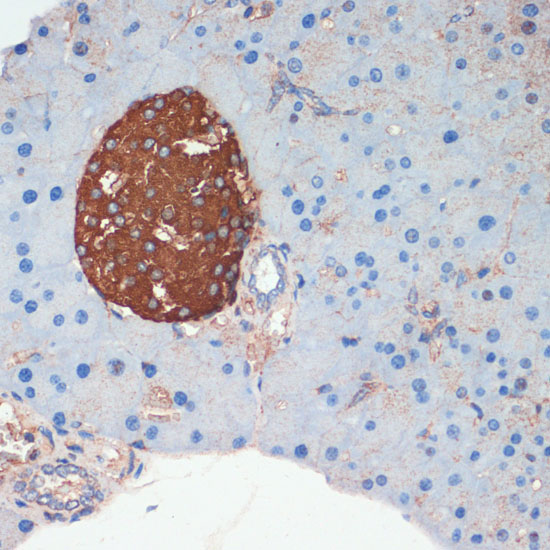

BackgroundThe hormone somatostatin has active 14 aa and 28 aa forms that are produced by alternate cleavage of the single preproprotein encoded by this gene. Somatostatin is expressed throughout the body and inhibits the release of numerous secondary hormones by binding to high-affinity G-protein-coupled somatostatin receptors. This hormone is an important regulator of the endocrine system through its interactions with pituitary growth hormone, thyroid stimulating hormone, and most hormones of the gastrointestinal tract. Somatostatin also affects rates of neurotransmission in the central nervous system and proliferation of both normal and tumorigenic cells.

ImmunogenA synthetic peptide corresponding to a sequence within amino acids 50 to the C-terminus of human SST (NP_001039.1).

ApplicationWB, IHC, IF, IP